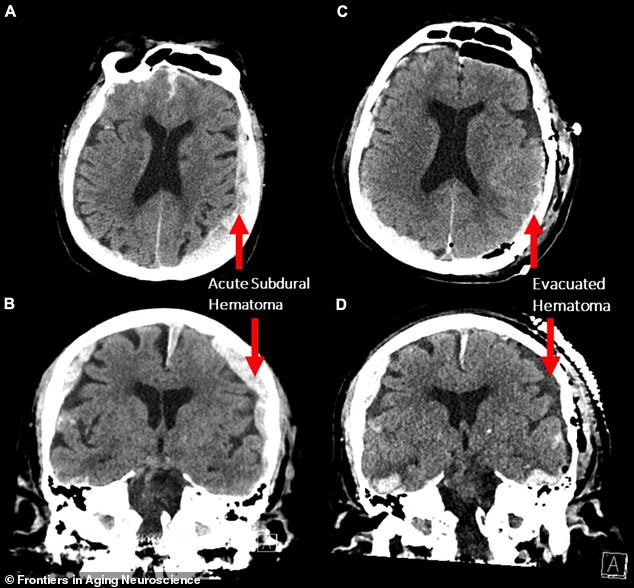

نجحوا علماء الأعصاب في رصد حالة الدماغ أثناء الموت بالصدفة لرجل عمره 87 قد توفي بسبب توقف مفاجئ للقلب، عندما كانوا يراقبون تخطيط المخ لتشخيص نوبات الصرع التي يعاني منها.